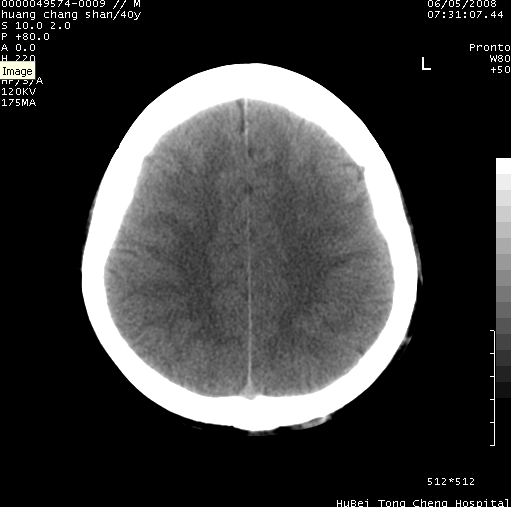

患者 m,40y。头痛,视力模糊,多饮多尿,性欲减退半年余。

行ct平扫+增强,图象如下:

肿瘤强化明显、鞍部骨质结构未见增大、破坏,考虑脑膜瘤可能性大

鞍背无破坏和明显受压,病变明显均匀强化,边界清晰。鞍上区脑膜瘤可能性大,不除外生殖细胞瘤。

平扫病灶呈等密度,增强后强化明显,均匀一致,结合病史首先考虑:垂体瘤。脑膜瘤不支持,因为脑膜瘤平扫多为实性呈均匀高密度影像,内分泌症状多不明显,垂体内分泌素测定正常。

鞍上池肿瘤,鞍背及垂体窝形态变化不明显,病灶强化密度均匀且高度强化,考虑实性颅咽管瘤、生殖细胞瘤及脑膜瘤可能。

结合临床考虑鞍上生殖细胞瘤可能性大于脑膜瘤(增强未见脑膜围征),建议结合冠状位扫描看病灶起源及垂体窝、鞍底情况。垂体窝内未见明显软组织密度影,垂体窝未见扩大,暂不考虑垂体瘤;病灶较大,未见囊变及钙化,颅咽管瘤不支持。期待结果!

1、头痛,视力模糊,多饮多尿,性欲减退半年余,提示:肿瘤为功能性肿瘤。

2、ct表现:肿瘤呈类圆形,均匀略高密度,无囊变,无钙化。侧脑室有扩大。

3、首先考虑:功能性垂体大腺瘤。

4、鉴别诊断:脑膜瘤,瘤体内点状钙化最具特征性,常位于鞍结节。颅咽管瘤,蛋壳样钙化,常有囊变。动脉瘤,位于鞍旁,强化与动脉一致。有时尚需与发生于鞍区的生殖细胞瘤鉴别,生殖细胞瘤钙化亦较常见。

5、友情提示:下回发现鞍区占位性病变,最好加扫冠状位,了解肿瘤与蝶鞍的关系及蝶鞍骨质的改变。